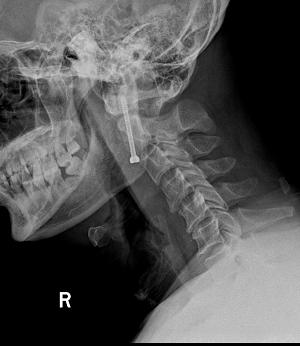

术中,手术团队对王先生颈部重要的组织结构均进行了较好的保护,而且一次性成功的置入空心钉固定骨折断端。手术持续了近5个小时,术后王先生症状明显缓解,无神经损伤。术后复查X线显示齿状突复位,螺钉位置良好。目前王先生已顺利出院,并对北京友谊医院骨科中心的服务进行了高度的评价。

术后显示齿状突复位,螺钉位置良好